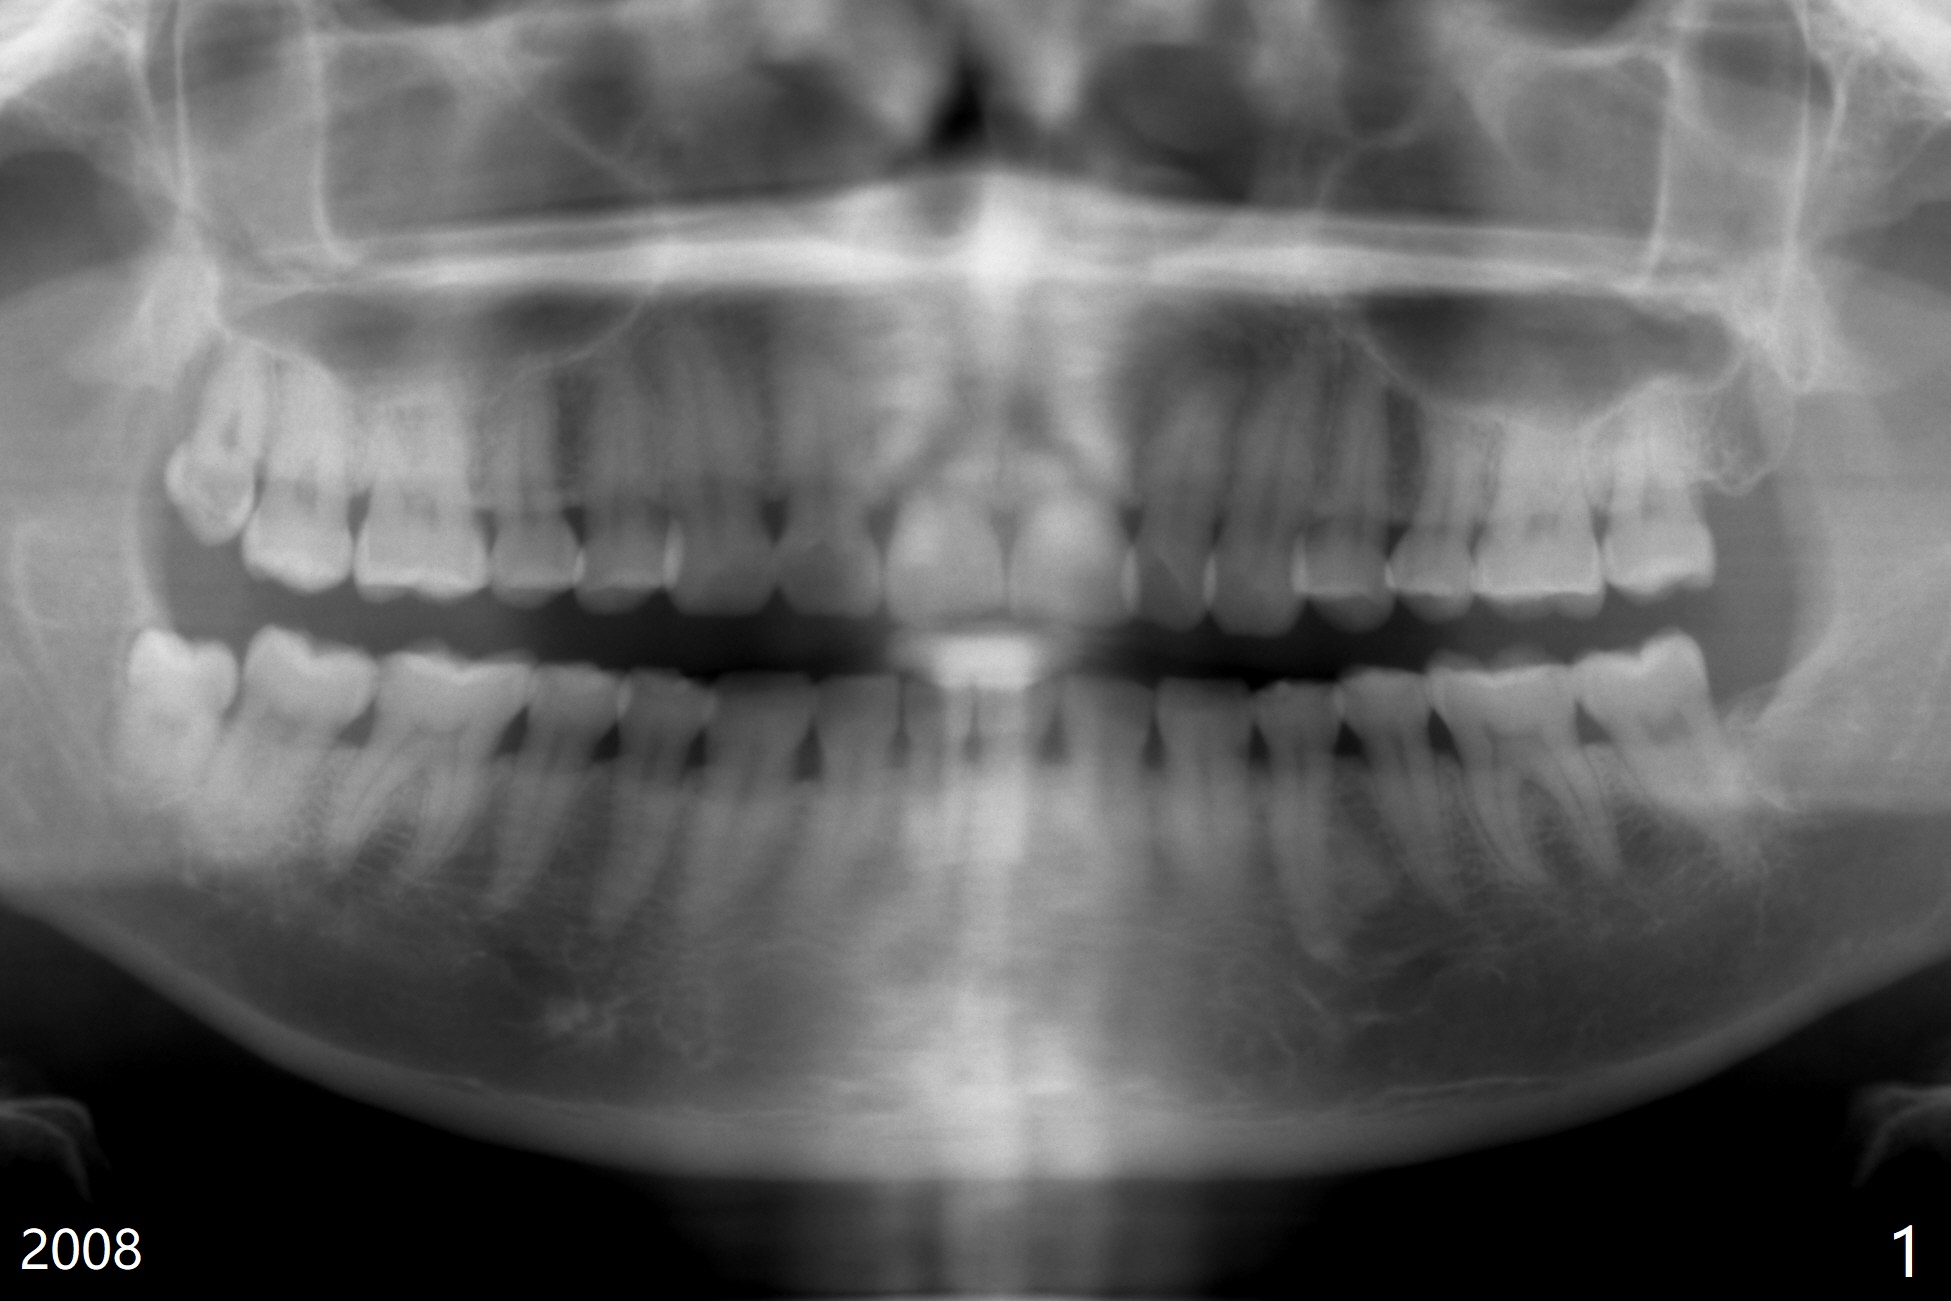

51岁女要求拔除#32(图一),劈牙两次,牙槽窝塞入胶原骨(Osteogen Plug),缝合,术后12天有不典型干槽症。术后2.5月第二,三磨牙之间牙槽嵴薄(图二:>),术后2年2个月#32牙槽窝密度高于#17(术后至少13年,图三)。